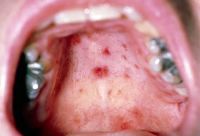

July 19, 2024 - Close-up of the inner lip with tiny blisters and open sores on the inner lip caused by hand, foot, and mouth disease. In the early stages, an HFMD rash will look like small pink dots.

The 1st symptoms of hand, foot and mouth disease can be: ... The rash of spots can look pink, red, or darker than the surrounding skin, depending on your skin tone. The spots can turn into blisters, which might be grey or lighter than surrounding skin and can be painful. Symptoms are usually mild and are the same in adults and children.

March 8, 2024 - The usual signs and symptoms of hand, foot, and mouth disease include fever and a characteristic rash on the hands, feet, and mouth. The rash typically consists of small, red bumps that may blister or ulcerate.